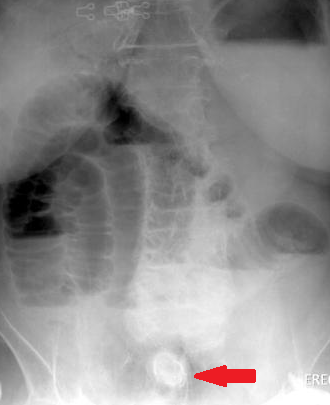

Plain abdominal radiographs. Small bowel loop distension. Red arrow — Radiopaque mass (gallstone) (Courtesy Dr. V. Penopoulos)